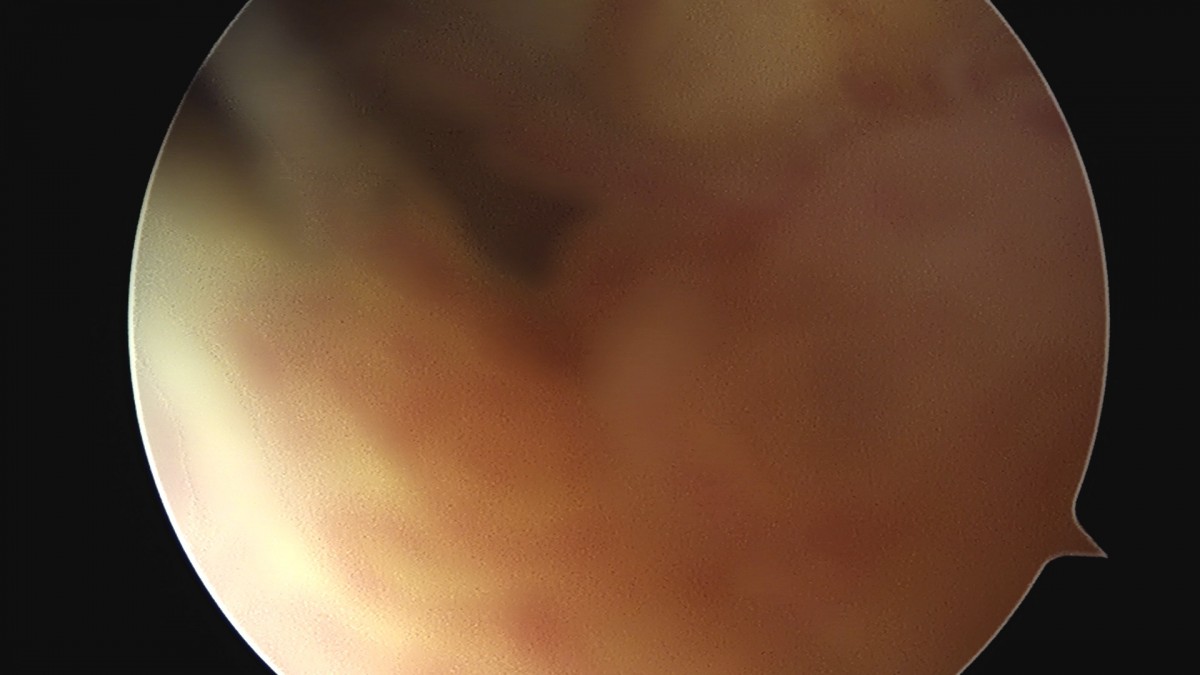

이재상원장님 무릎 전방십자인대 재건술 및 반월상 연골판 절제술 유해O 환자

dae765e4d9ac96aee867c9d6292d8784_1758007656_9699.jpg